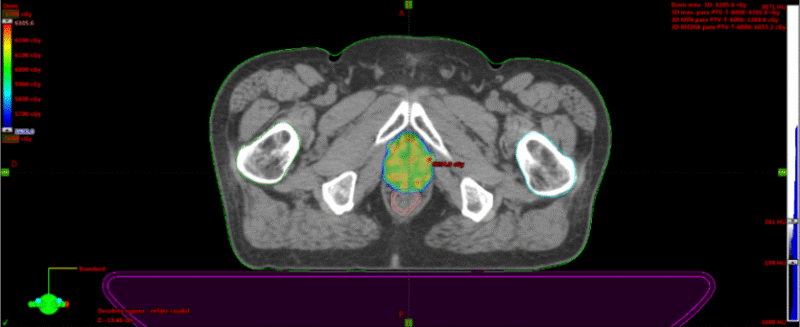

Fig. 2c. Técnica de IMRT (Radioterapia de intensidad modulada). Se observa en los colores las dosis de radiación sobre la pelvis (verde y azul, 46Gy) y sobre la próstata (naranjo, 70Gy). En el gráfico, las líneas de colores corresponden a los órganos de riesgo (OAR) y los target, en donde se mide la dosis de radiación, en un volumen determinado que llega al OAR, para así saber que está en rangos de buena tolerancia (ya predeterminados) y que las zonas target reciban al menos las dosis mínimas terapéuticas. Las dosis están en cGy (70Gy= 7000cGy).